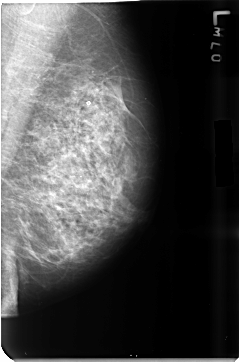

B_3500_1.LEFT_MLO

LEFT_MLO LINES 4696 PIXELS_PER_LINE 3104 BITS_PER_PIXEL 12 RESOLUTION 50 NON_OVERLAY